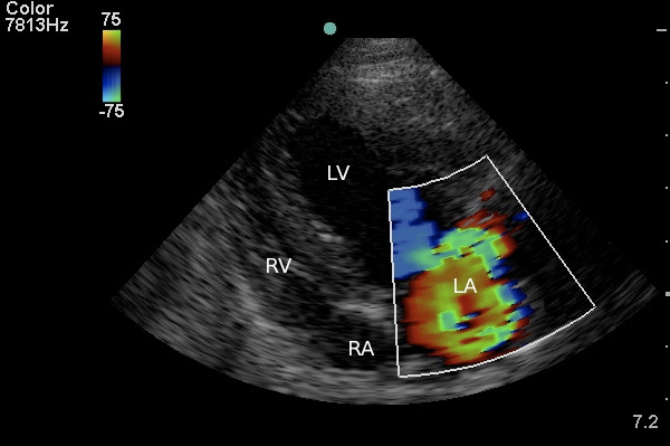

• Evaluate valve structure and regurgitation

• Degenerative mitral valve disease